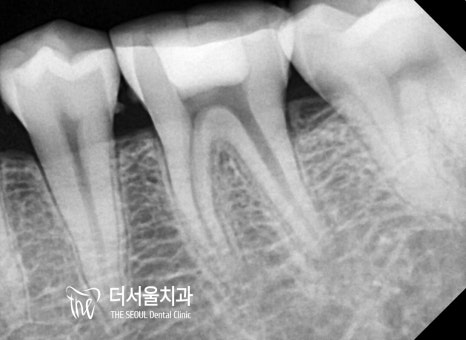

『뿌리 끝까지 빼곡하게

채워진 모습이 관찰되시나요?ㅎㅎ』

이렇게 확실하게 채워져 있어야

신경치료의 결과를 기대해 볼 수 있습니다.